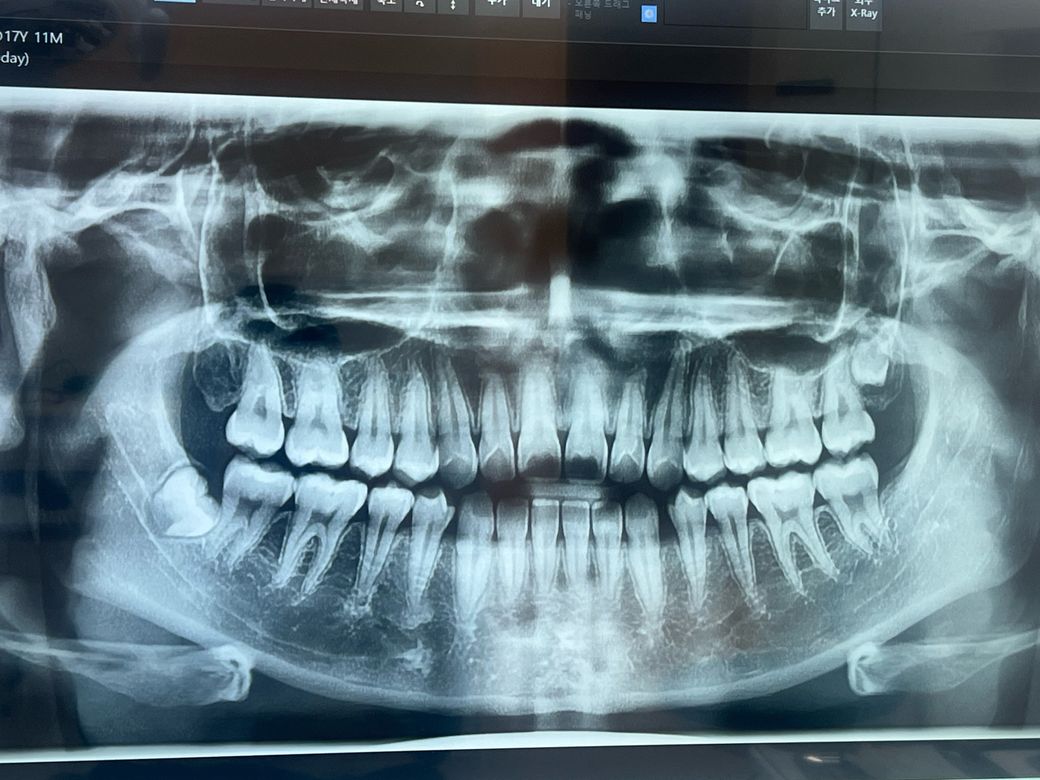

치과 엑스레이 어떻게 봐야 하나요??

사진으로 봤을 땐 아랫쪽 사랑니가 왼쪽에 있잖아요 그럼 실제로는 제 오른쪽 밑에 사랑니가 있는 건가요? 아님 사진 그대로 왼쪽 밑에 사랑니가 있는 건가요?

파노라바 사진은 방향이 반대가 됩니다. 사진의 왼쪽이 실제 오른쪽이며 사진의 오른쪽이 실제 왼쪽의 이미지 입니다.

파노라마 엑스레이 사진은 좌우대칭입니다 지금 사진의 사랑니는 실제로는 오른쪽 아래 사랑니입니다

사진상으로 왼쪽 아래 오른쪽 위에 사랑니가 있는거 같습니다. 아직은 잇몸뼈 안쪽에 치아가 자라나고 있는상태 같습니다.